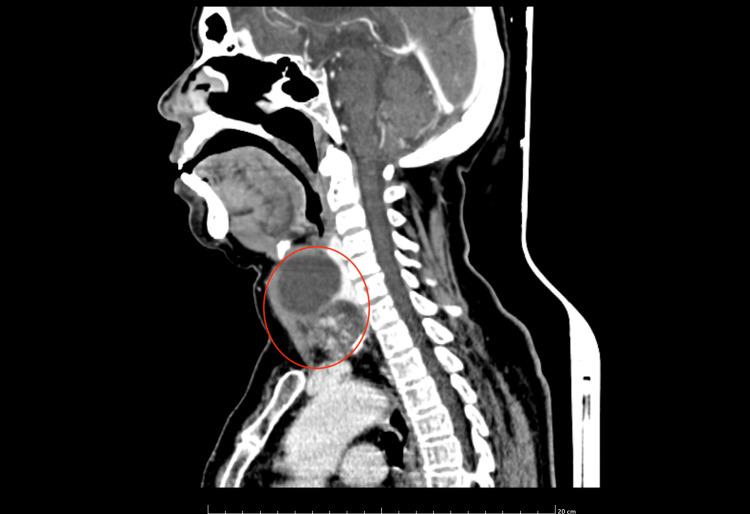

The incidence of mixed thyroid carcinoma of poorly differentiated thyroid carcinoma (PDTC) and papillary carcinoma thyroid is very unusual. PDTC exhibits a high degree of dedifferentiation and histopathological confirmation is done based on Turin's criteria. This type of carcinoma has a poor prognosis and the survival rates at five and ten years post-diagnosis are significantly lower compared to well-differentiated thyroid carcinomas. Surgery is the best mode of treatment at present. This is a case of a 71-year-old female who underwent total thyroidectomy with modified radical neck dissection which yielded a histopathological variant comprising PDTC and papillary thyroid carcinoma. The patient was followed up with a serial thyroglobulin antibody test and ultrasound of the neck at six months and one year, and both were found to be normal.

摘要

低分化甲状腺癌(PDTC)与甲状腺乳头状癌混合性甲状腺癌的发病率非常罕见。PDTC表现出高度的去分化,组织病理学诊断依据都灵标准进行。这种类型的癌预后较差,与高分化甲状腺癌相比,诊断后5年和10年的生存率显著降低。目前手术是最佳治疗方式。这是一例71岁女性患者,接受了全甲状腺切除术及改良根治性颈清扫术,术后病理结果为PDTC与甲状腺乳头状癌的组织病理学变异型。对该患者在术后6个月和1年进行了系列甲状腺球蛋白抗体检测及颈部超声检查进行随访,结果均正常。